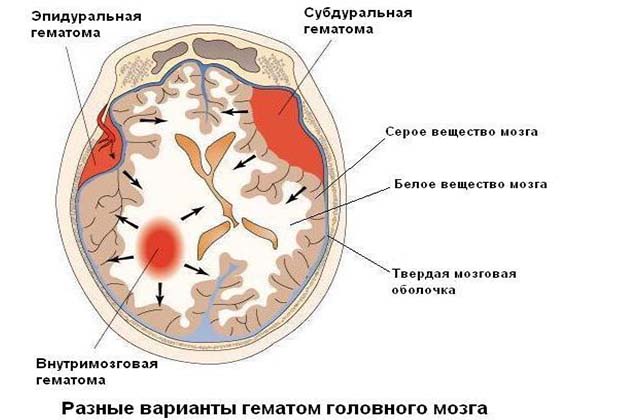

В зависимости от места локализации и вида последствия после гематомы на голове у новорожденного могут быть разными.

Гематома эпидуральная

Такие образования возникают из-за разрыва сосудов, находящихся между мозговой оболочкой и черепной костью. Если диагностирована эпидуральная гематома у новорожденного после родов, последствия ее довольно опасны. Уже через 5-7 часов в мозговых тканях может возникнуть существенное их сдавливание, вследствие чего состояние малыша стремительно ухудшается.

По форме образования эпидурального типа похожи на линзу 3-8 см в диаметре. По степени тяжести различают три формы:

Гематомы субдуральные

При разрывах сосудов между мягкой и твердой оболочкой черепной коробки образуется гематома в голове после родов у новорожденного, которая называется субдуральной.

Внутримозговая гематома

Внутримозговые кровоизлияния влекут за собой повреждение нервных клеток и способны полностью или частично разрывать нервно-мышечные связки. Очень часто такого типа гематома головы у новорожденного при родах проявляется двумя или большим количеством кровоподтеков.

В зависимости от глубины поражения тканей родовая гематома на голове у новорожденного подразделяется:

У новорожденных гематома на голове после родов также делится на такие виды:

- кефалогематома — в результате повреждения сосудов и образование кровяных сгустков между надкостницей и черепом;

- внутримозговая — образование из крови внутри мозга;

- эпидуральная — сгусток крови между костью черепа и оболочкой мозга, относится к самой опасной;

- субдуральная — попадание крови под оболочку мозга.

Виды образований

Новообразования в области головы у ребенка, возникшие при родах, разделяют на несколько видов. Отличие – лишь в точном месте сосредоточения новообразования. Исходя из этого, можно выделить кефалогематому и другие разновидности гематом:

- кефалогематома – кровоизлияние в зону между надкостницей и костями головы;

- эпидуральная – кровяное скопление между костями черепа и твердой мозговой оболочкой;

- внутримозговая – проникновение крови в полость головного мозга;

- субдуральная – кровоизлияние в область между твердой и арахноидальной оболочками.

Специалисты выделяют несколько разновидностей гематом у младенцев:

- Кефалогематома. Скопление крови наблюдается между черепом и надкостницей. Встречается нечасто, у 2% малышей.

- Эпидуральная. Гематома образуется между черепной костью и твердой мозговой оболочкой. Очень тяжелый и опасный вид кровоизлияния.

- Внутримозговая. Кровь проникает в головной мозг, что вызывает тяжелое состояние у ребенка.

- Субдуральная. При этом кровь попадает под твердую мозговую оболочку.

Различают такие виды гематом у новорожденных: